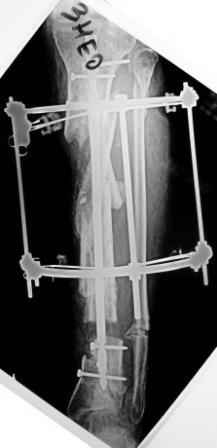

2) После репозиции более очевидна стала проблема дефекта кости в верхней трети голени, два фрагмента свободно лежат. Остановились на варианте перехода на интрамедуллярный синтез стержнем с покрытием костный цемент+ванкомимцин и замещении дефекта с помощью транспорта фрагмента (рис 2)